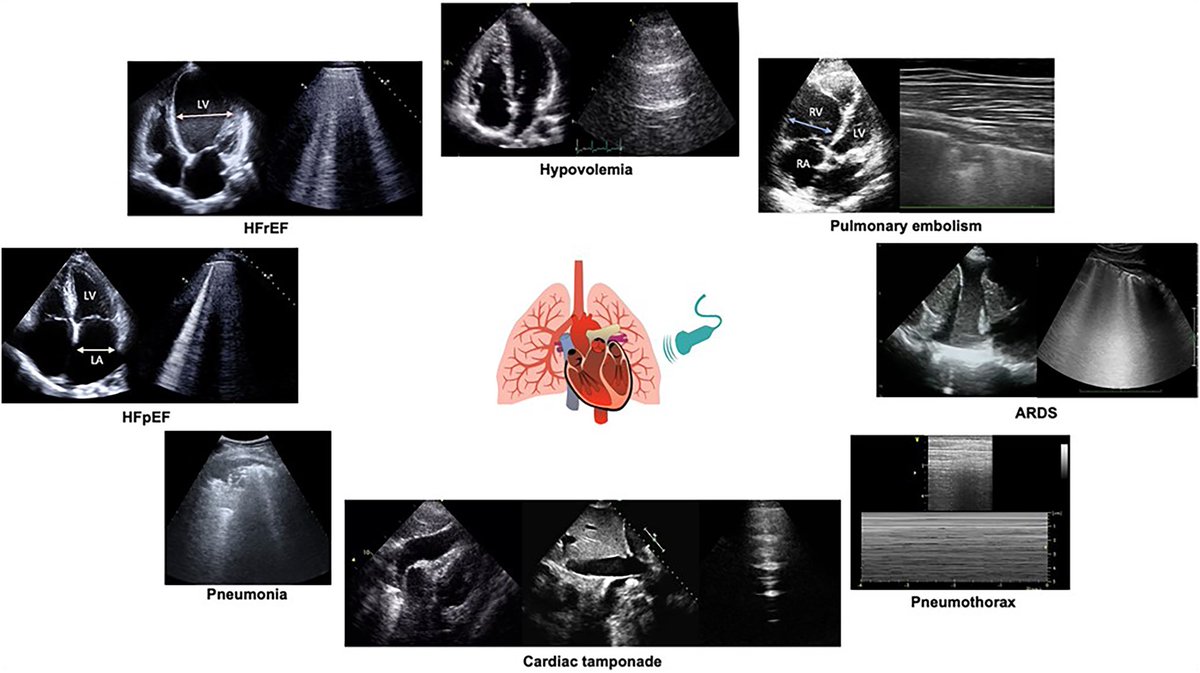

Also from the #EACVI consensus statement on lung #ultrasound in heart failure, the authors include an infographic highlighting the idea of integrating both cardiac and lung ultrasound findings into the clinical picture #POCUS #echo 🔗 https://t.co/XEzWd7QKff